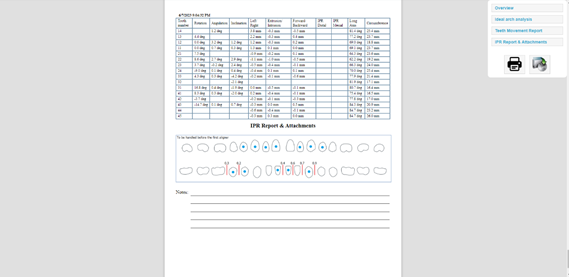

Slika 8. Ako smo zadovoljni sa segmentacijom zuba, obavezno proučavamo uputstva ortodonta koji bi nam morao dati točnu informaciju na kojim zubima i na kojim pozicijama želi da postavimo tzv. attachmente. Attachmenti su mali kompozitni oblici koji se apliciraju na zube koje je ortodont procijenio da su najoptimalniji za postavu attachmenta. Oni u kombinaciji sa udlagom znatno pospješuju pomake zuba te s njima možemo očekivati bolje, stabilnije I brže rezultate. Oblik attachmenta može biti raznoliki i također ovdje ortodont mora odabrati oblik attachmenta koji mu najviše odgovara. Također postoji i mogućnost dimplingsa koji umjesto attachmenta koji se lijepe na zub služe kao negativi u udlagi koji jače guraju zub u željenom smjeru.

Slika 11. I 12. Kada svi uključeni u terapiju odobre sve pomake I krajnje rezultate na temelju videa, slika I ortho reporta koji nam prikazuje sve odrađene pomake pojedino po zubu, pojedino po svakoj fazi udlage I ortodontu gdje se trebaju postaviti attachmenti dalje nastavljamo sa izradom alignera gdje generiramo modele koje printamo I na Kojima termoformiramo udlage.